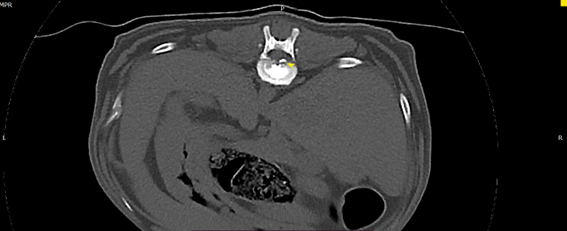

• 狗狗後腳癱瘓也有可能是血栓 不一定是骨骼神經肌肉問題喔

狗狗後腳癱瘓也有可能是血栓 不一定是骨骼神經肌肉問題喔